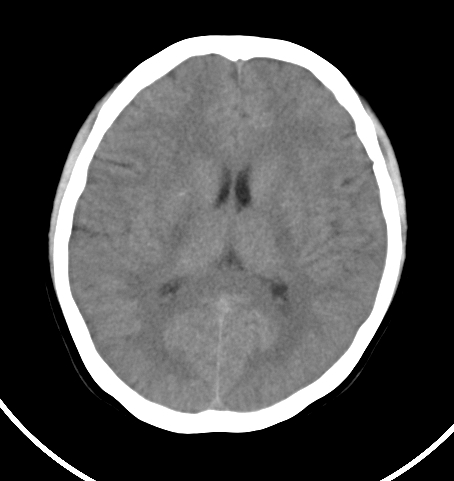

病人女 35岁 自述头晕 头痛

双侧基底节区及右侧丘脑区多发点状钙化,周围未见水肿及占位征象.余未见明显异常.考虑:脑囊虫病<囊虫的退变或死亡期>请结合有无相关病史.

以下是引用苯小孩在2007-4-20 15:47:00的发言:[br]双侧基底节区及右侧丘脑区多发点状钙化,周围未见水肿及占位征象.余未见明显异常.考虑:脑囊虫病<囊虫的退变或死亡期>请结合有无相关病史.

颅内有散在钙化

脑囊虫病理性钙化。